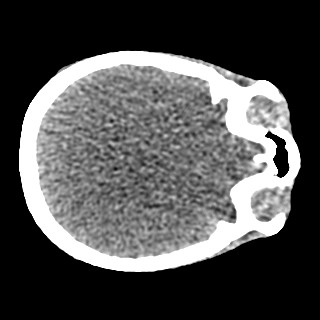

Cone-beam CT (CBCT) employs a flat-panel detector to achieve three-dimensional imaging with high spatial resolution. However, CBCT is susceptible to scatter during data acquisition, which introduces CT value bias and reduced tissue contrast in the reconstructed images, ultimately degrading diagnostic accuracy. To address this issue, we propose a deep learning-based scatter artifact correction method inspired by physical prior knowledge. Leveraging the fact that the observed point scatter probability density distribution exhibits rotational symmetry in the projection domain. The method uses Gaussian Radial Basis Functions (RBF) to model the point scatter function and embeds it into the Kolmogorov-Arnold Networks (KAN) layer, which provides efficient nonlinear mapping capabilities for learning high-dimensional scatter features. By incorporating the physical characteristics of the scattered photon distribution together with the complex function mapping capacity of KAN, the model improves its ability to accurately represent scatter. The effectiveness of the method is validated through both synthetic and real-scan experiments. Experimental results show that the model can effectively correct the scatter artifacts in the reconstructed images and is superior to the current methods in terms of quantitative metrics.